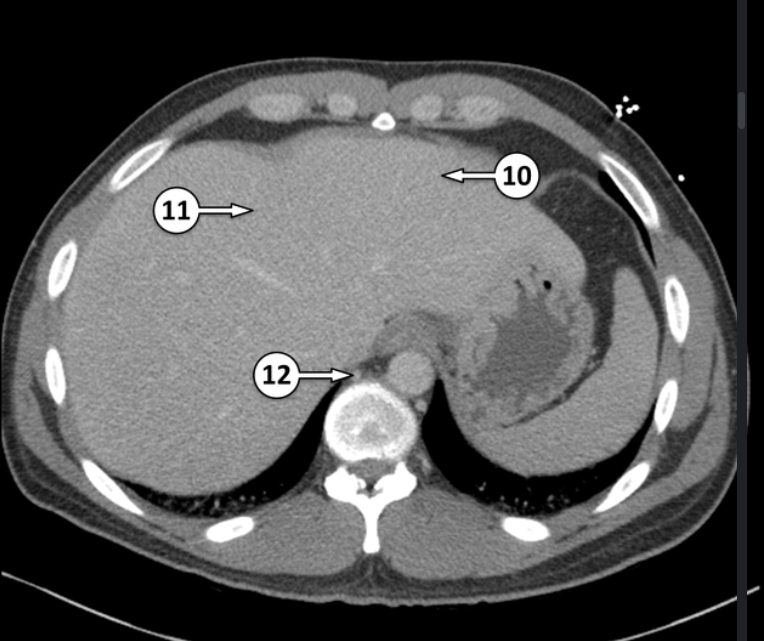

10 and 11 are segments of the liver. Label which segments they are

segment II of the liver

segment IV of the liver